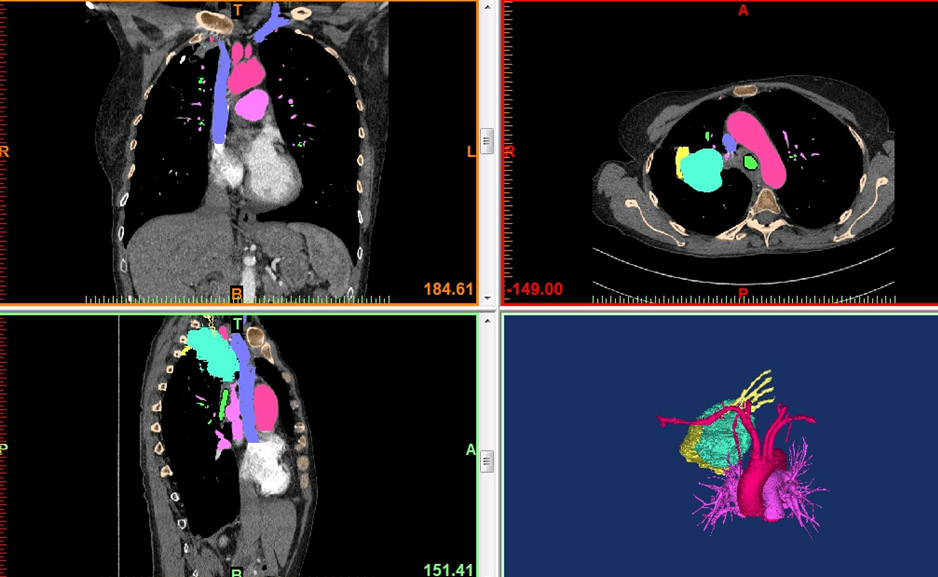

The process of 5D printing was developed to incorporate change in tumor size after neoadjuvant therapy in anatomic models used for surgical planning. Pre-treatment CT and PET scans are reformatted and fused. Crucial anatomy from these studies, along with post-treatment CT and MR, are coregistered. The fused anatomy is converted into stereolithography(STL) files for 3D printing.

A patient presenting with a complex thoracic tumor was selected for trial 5D printing. 3D and 5D models were prepared to allow surgical teams to directly evaluate and compare the added benefits of information provided by printing in 5D.

Printing 5D models in patients with complex thoracic pathology facilitates surgical planning, selecting margins of resection, anticipation of potential difficulties, and education for residents and patients.